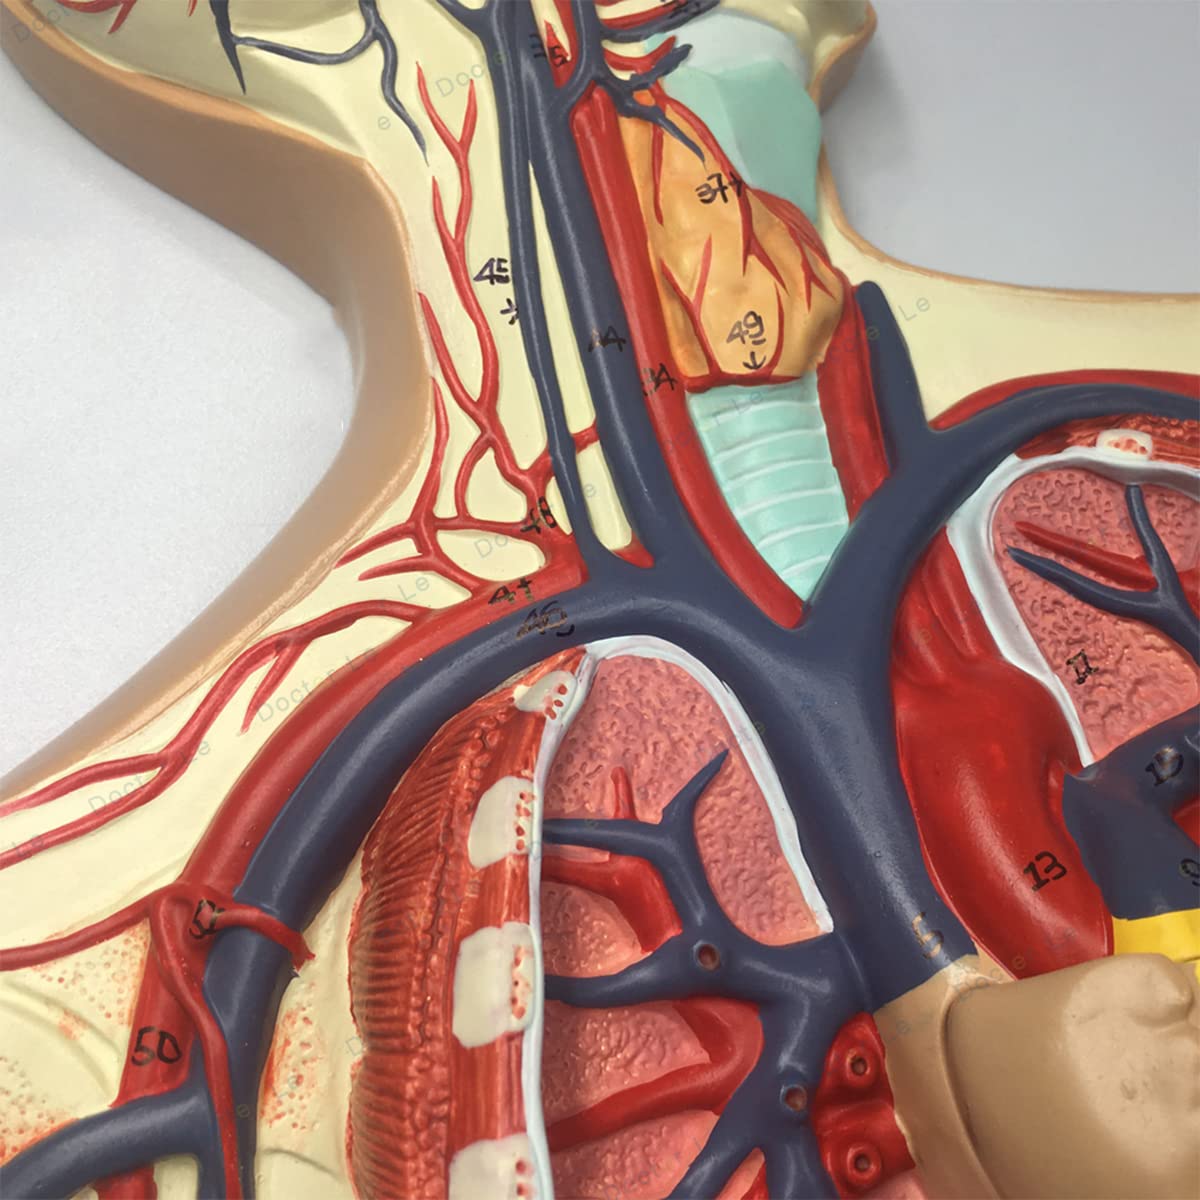

- Features: This model shows the structure of blood circulation in various parts of the human body. The circulatory system is the channel through which blood flows in the body and is divided into two parts: the cardiovascular system and the lymphatic system. Blood circulation route: superior and inferior vena cava → right atrium → right ventricle → pulmonary artery - → alveolar surrounding → pulmonary veins - >> left atrium → left ventricle → aorta - → systemic tissues (except lung). Product Size: Using this model helps to understand the composition and structure of human blood circulation. The size of the model is 1/2 the size of the human blood circulatory system. Product size: 90*30 cm/35.4*11.8 inches. High Quality: High-quality prototypes, sturdy hand-made, not fragile, made of high-quality environmentally friendly PVC, fine workmanship, creating good objects with clear shapes and rich details. Meticulous workmanship: The model has meticulous workmanship, realistic details, clear texture, easy to use and easy to observe. This product comes with a base, which is convenient for learning and teaching. Good Teaching Aids: This collection is designed for anatomy professionals and students. We are sure you will love these models. Can also be given as a gift to educators or doctors, excellent educational tool for students/teachers/professionals.

Product Specifications:Product name: Human Blood Circulatory System Model Product Type: Medical Teaching Model Product material: PVCProduct use: medicine, school, hospital, medical giftPackage list:Human Blood Circulatory System Model *1Notice:The monitor calibration is different, and the color of the object shown in the photo may be slightly different from the actual product. Please refer to the actual product.